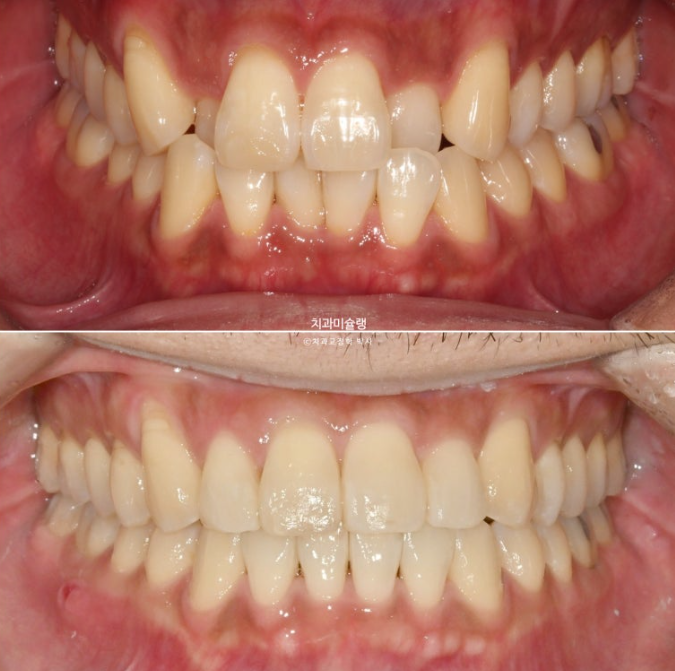

덧니가 있고 위아래 치아 중심선이 어긋나 있습니다.

치아중심선이 어긋나 있는 것은 아래턱 비대칭이 있기 때문입니다.

그에 비해 뒤쪽 어금니 교합은 좋은 편 입니다.

전 후 비교 보겠습니다.

24.07~25.10

악궁확장 기간을 포함하여 총 치료기간은 1년 3개월입니다.

중심선의 개선과 덧니의 해소